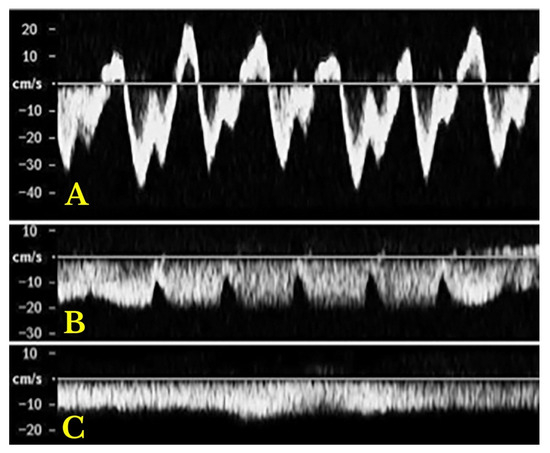

Assessing Venous Congestion in Acute and Chronic Heart Failure: A Review of Splanchnic, Cardiac and Pulmonary Ultrasound: Part 1: Conventional B-Mode, Colordoppler, and Vexus Protocol

Background/Objectives: Heart failure (HF) causes systemic and regional haemodynamic alterations that extend beyond the heart, profoundly affecting splanchnic circulation. Venous congestion is a hallmark of heart failure (HF) and a major determinant of clinical deterioration and multiorgan dysfunction. The splanchnic venous system—comprising [...] Read more.

Background/Objectives: Heart failure (HF) causes systemic and regional haemodynamic alterations that extend beyond the heart, profoundly affecting splanchnic circulation. Venous congestion is a hallmark of heart failure (HF) and a major determinant of clinical deterioration and multiorgan dysfunction. The splanchnic venous system—comprising the portal, hepatic, and renal veins—acts as a key reservoir for intravascular volume redistribution. Conventional ultrasound (US), using grayscale and Doppler imaging, offers a direct, non-invasive approach to visualize these haemodynamic changes. This review, Part 1 of a two-part series, summarizes the current evidence and clinical applications of conventional US for assessing splanchnic, cardiac and pulmonary vascular alterations in patients with HF. Methods: A systematic review was performed in PubMed, Embase, and the Cochrane Library up to current date, following PRISMA 2020 guidelines. Eligible studies included adult human investigations evaluating splanchnic vascular changes in HF using B-mode, color Doppler, or pulsed Doppler ultrasonography. Exclusion criteria were pediatric, animal, or non-English studies and non-standard imaging methods. Data on ultrasonographic parameters, haemodynamic correlations, and prognostic value were extracted and qualitatively synthesized; Results: A total of 148 eligible studies (n ≈ 7000 patients) demonstrated consistent associations between HF severity and alterations in splanchnic, cardiac and pulmonary flow. Findings included increased bowel wall thickness, portal vein dilation with elevated pulsatility, and monophasic or reversed hepatic vein waveforms, all correlating with higher right atrial pressure and adverse clinical outcomes. The integration of these parameters into the Venous Excess Ultrasound (VExUS) framework enhanced detection of systemic venous congestion, in addition to the study of the cardiac and pulmonary circulation. Conclusions: Conventional ultrasound assessment of splanchnic vasculature provides valuable, reproducible insight into systemic congestion in HF. Incorporating hepatic and portal Doppler indices into standard evaluation protocols may improve risk stratification, optimize decongestion therapy, and guide management. Further prospective randomized and outcome-driven studies are required before VExUS-based therapeutic thresholds can be universally recommended and define prognostic thresholds. Full article